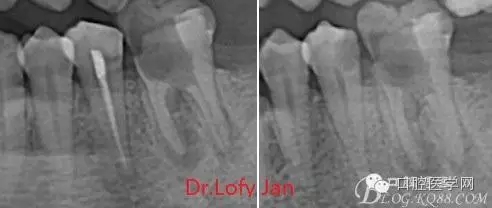

《數(shù)字化根尖片、曲面斷層片、CBCT測量牙齒長度準(zhǔn)確性的比較研究》文中顯示:平行投照數(shù)字化根尖片影像長度和牙齒實際長度之間無顯著性差異(P0.05);數(shù)字化曲面斷層片影像長度和牙齒實際長度之間有顯著性差異(P0.05),平均失真率為17.05%。CBCT冠狀面測量結(jié)果中除上頜前磨牙區(qū)、下頜前磨牙區(qū)與真實長度差異無統(tǒng)計學(xué)意義(P0.05)外,其余6個分區(qū)差異均有統(tǒng)計學(xué)意義(P0.05);矢狀面測量結(jié)果中上頜磨牙區(qū)、下頜磨牙區(qū)、下頜前磨牙區(qū)、下頜尖牙區(qū)、下頜前牙區(qū)與真實長度比較差異均有統(tǒng)計學(xué)意義(P0.05)。結(jié)論平行投照數(shù)字化根尖片較曲面斷層片和CBCT能更加精確地反映牙齒的真實長度。

病例分析:曲面斷層片在x線輔助診斷與檢查中目前大多數(shù)文獻(xiàn)和著作都建議只能作為初診拍片檢查手段,不能作為終末疾病的確診與手術(shù)療效的評價指標(biāo),臨床大部分中小型門診都因為設(shè)備不齊全導(dǎo)致信息偏差很大。